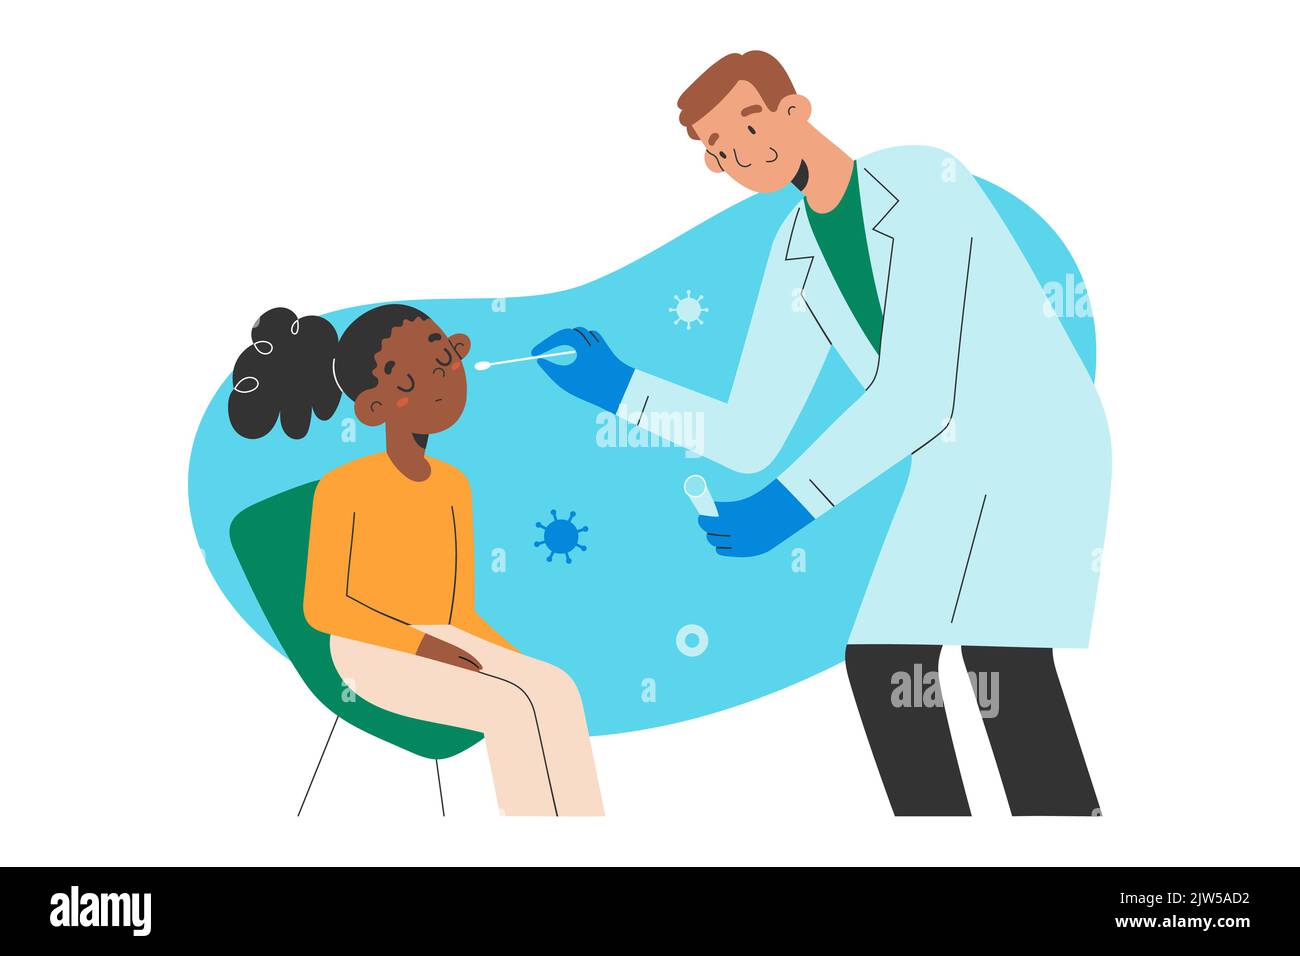

RF2BY648K–Test Covid, médecin recueille le mucus nasal par échantillon d'écouvillon pour l'infection à Covid-19, patient testé, analyse de laboratoire, examen médical, vecteur de dessin animé plat

RF2JW5AD2–Enfants covid19 test. Médecin amical utilisant un coton-tige pour tester une fille afro-américaine pour le coronavirus, illustration vectorielle